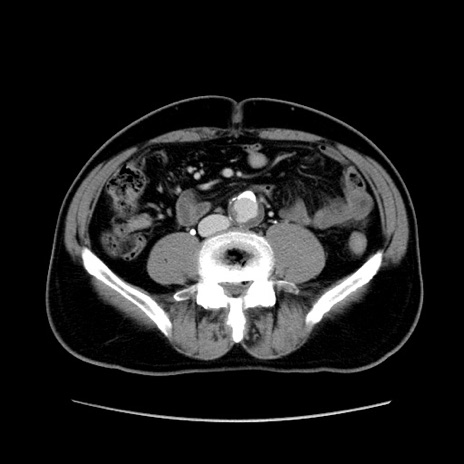

症例34(横断像)

【症例】60歳代 男性

【主訴】右鼠径部膨隆

【現病歴】1年程前より右鼠径部膨隆あり。自己にて還納可能だったため放置していた。3時間前より右鼠径部の脱出を認め、還納困難となり受診。

【既往歴】高血圧

【身体所見】右鼠径部に小児頭大の膨隆あり。弾性硬であり、用手還納は困難。左鼠径部にも膨隆を認める。脱出はなし。

【データ】WBC 15500、CRP 測定なし